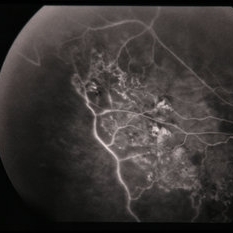

BRVO - Massive Exudate from Collaterals

Feb 24 2014 by David Callanan, MD

66-year-old female with BRVO - massive exudate from collaterals, 20/70 OD; 20/25 OS in 1985; +HTN, glaucoma; 20/200 OD 1987.

Condition/keywords: branch retinal vein occlusion (BRVO), collaterals, exudate